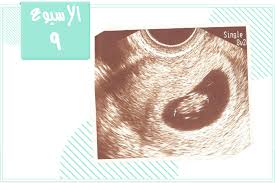

تكو ن الجنين الأسبوع التاسع من الحمل بيبي سنتر آرابيا

تكو ن الجنين الأسبوع التاسع من الحمل أنا مامي

تكو ن الجنين الأسبوع التاسع من الحمل موسوعة